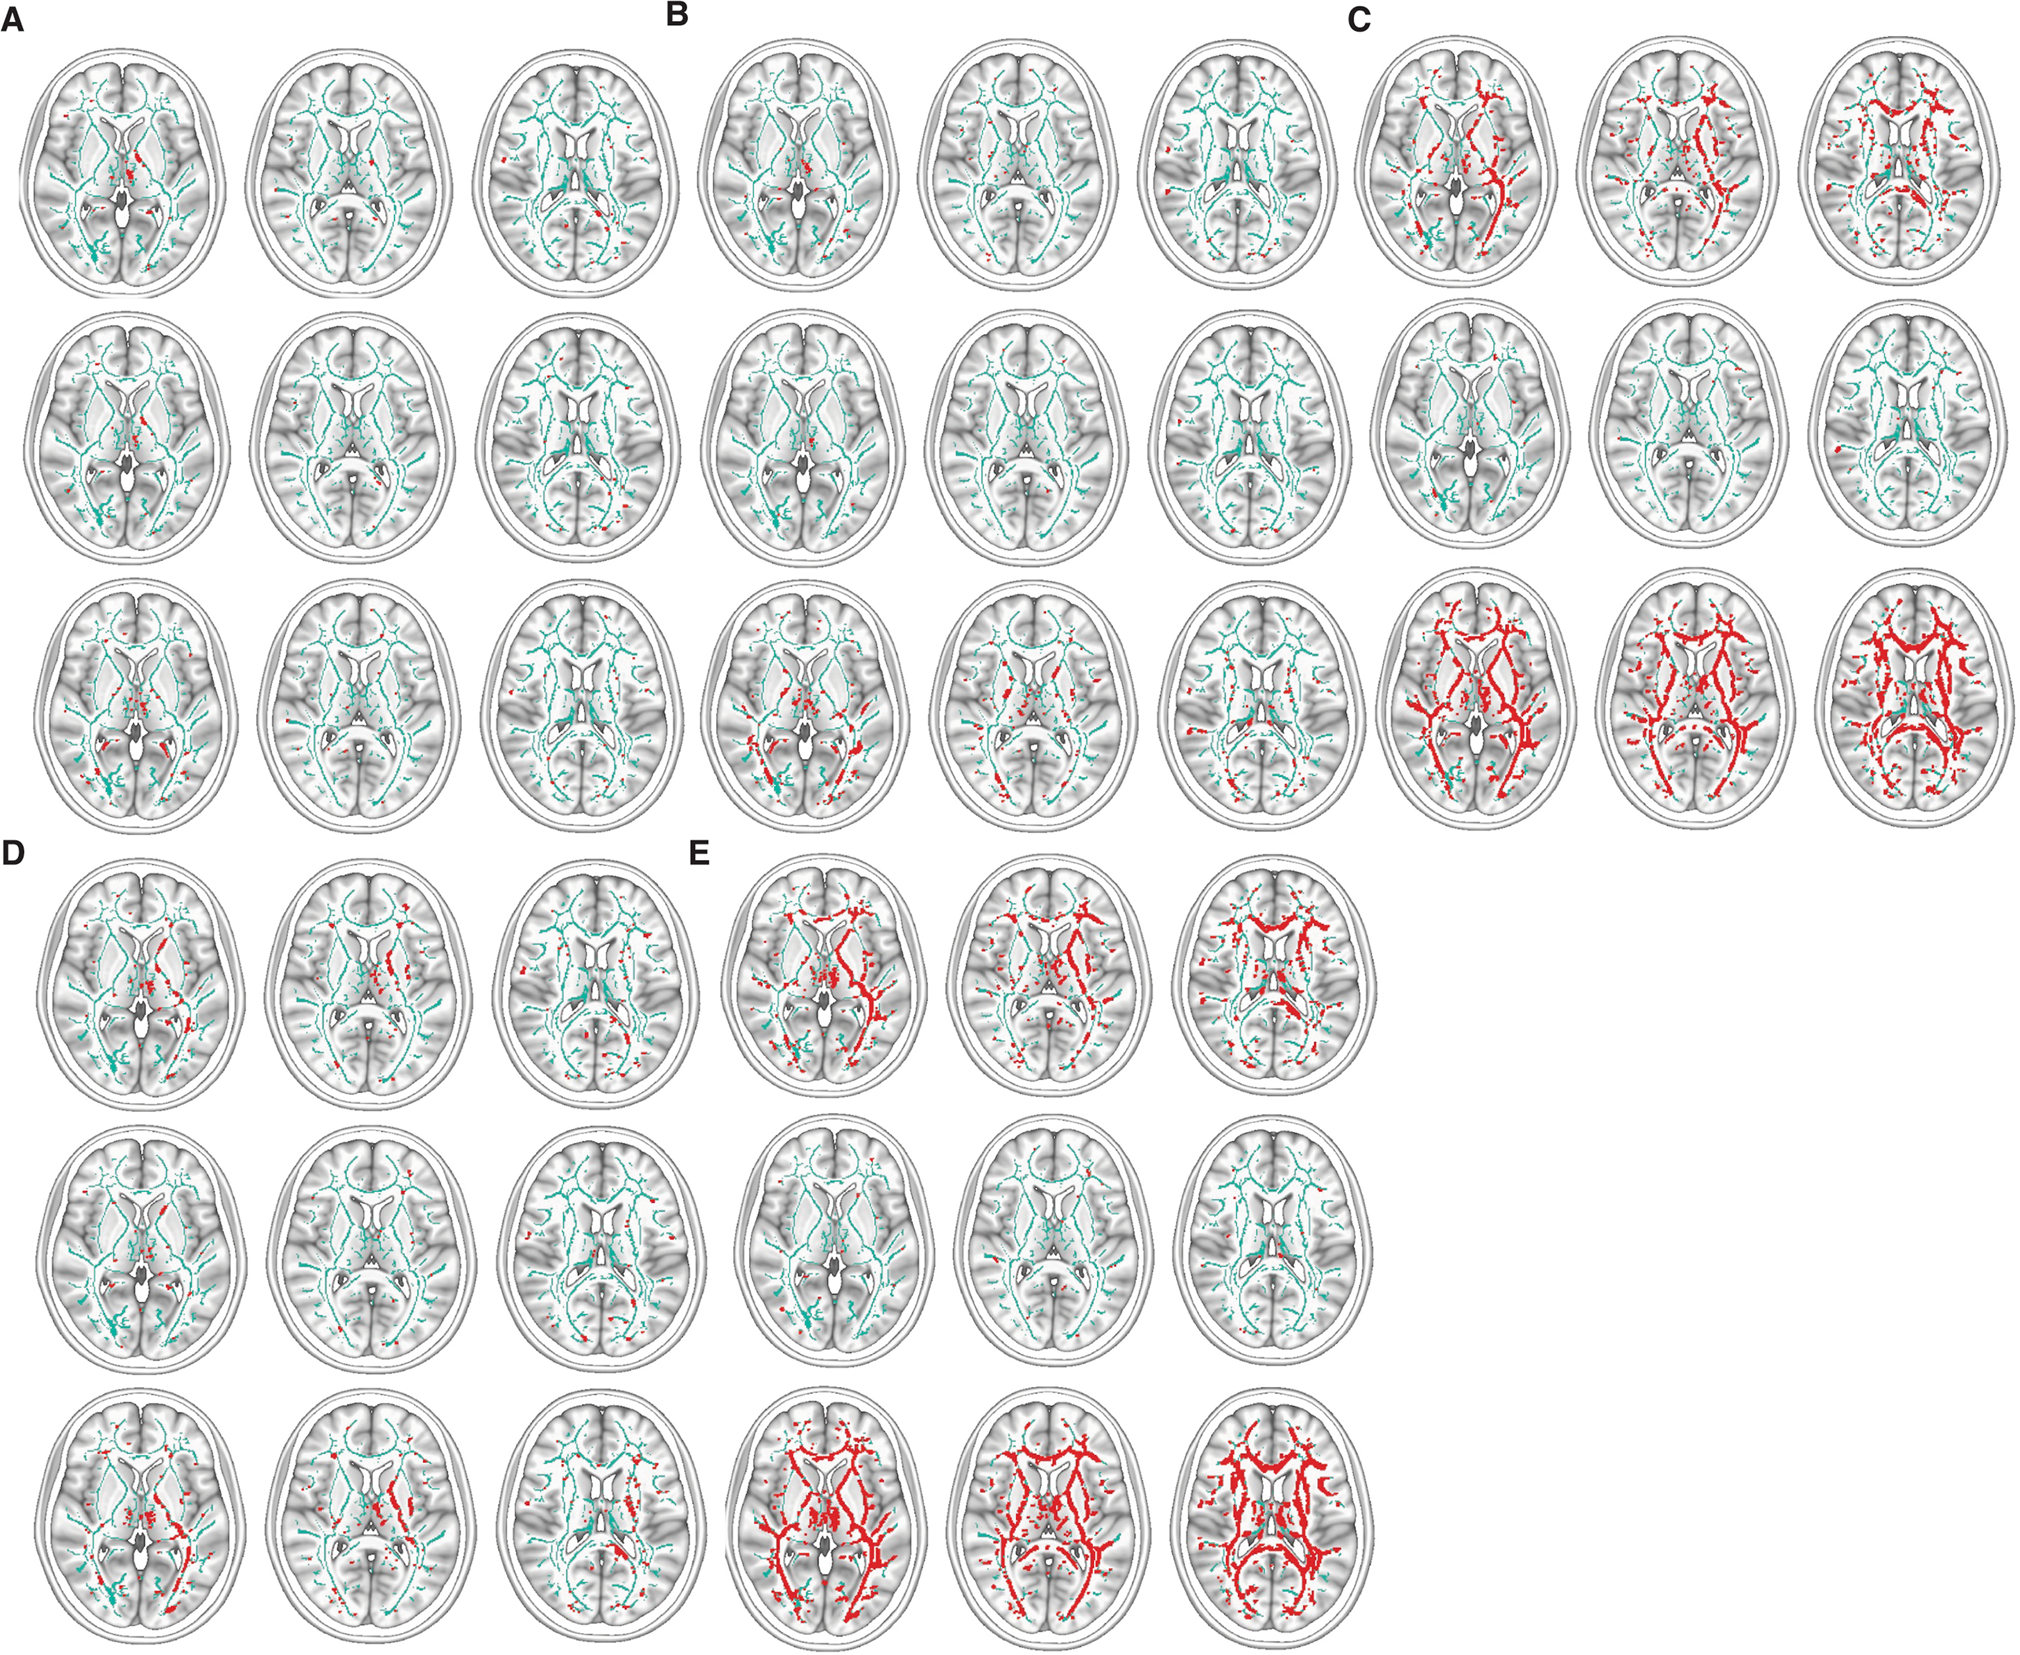

Fig. 4: TBSS low FA images corresponding to each rsFC group.

Low FA is red when p < 0.05 adjusted for multiple comparisons of voxels. The images are arranged for the whole group (top row), BP subjects (middle row), and SZ subjects (bottom row) of each group. A–E represent each of the five sets that describe different patterns of connections among the nodes: A the Avoidant-Anhedonic (group 1), B the Sensitive-Disorganized subjects (group 2), C the Asocial-Blocked subjects (group 3), D the Fragile-Avolitional subjects (group 4), and (E) the Explosive-Inattentive individuals (group 5).